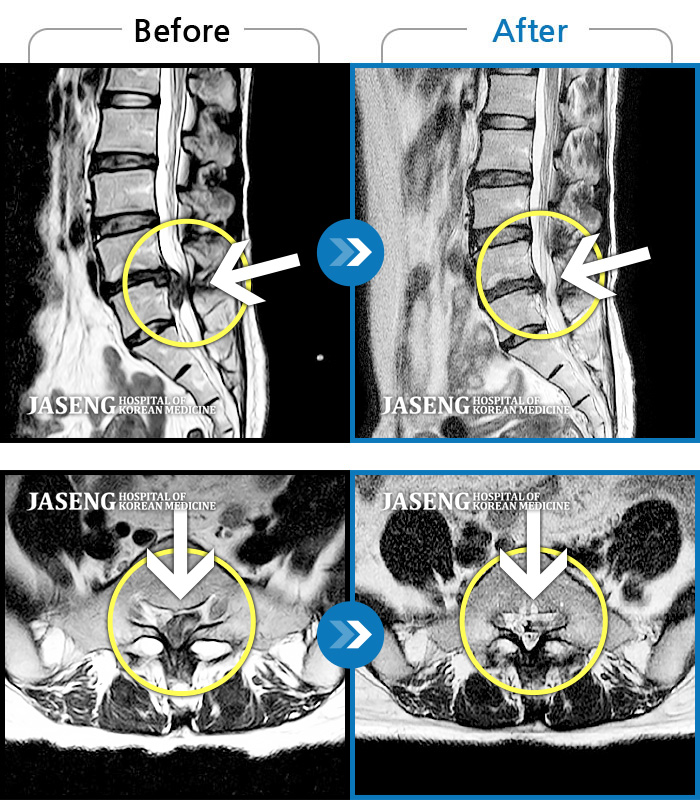

Before

After

통증 및 우측 엉치 우측 종아리 땡기는 통증이 심하여 일상생활이 안되는 상태로 내원하셨던 분입니다.

2023.11.21 ~ 2024.06.05